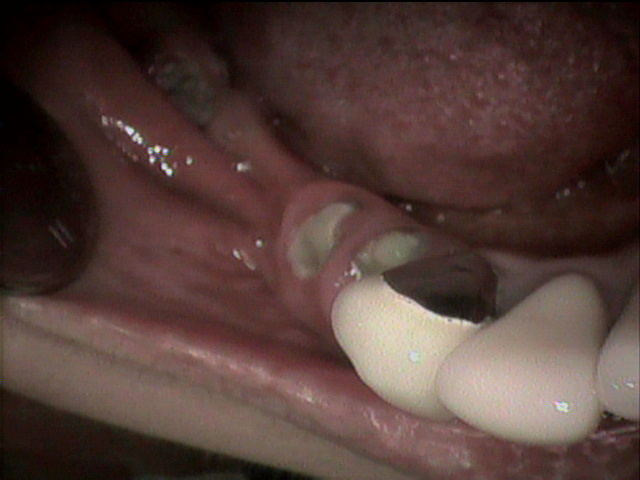

84歳女性のKさんは、下の顎が総入れ歯で、顎の状態が骨が少なく、

状態がよくないために、顎が入れ歯で痛くなりやすく、

コンフォート義歯を入れています。今回上の総入れ歯がやせてきてしまい、

新しく作製しました。上の顎の顎堤の状態は良好ではありませんが、

精密義歯で、いつでも顎の状態の変化に対応できる入れ歯を作製しました。

上の総入れ歯のコンフォート加工の症例です。 |